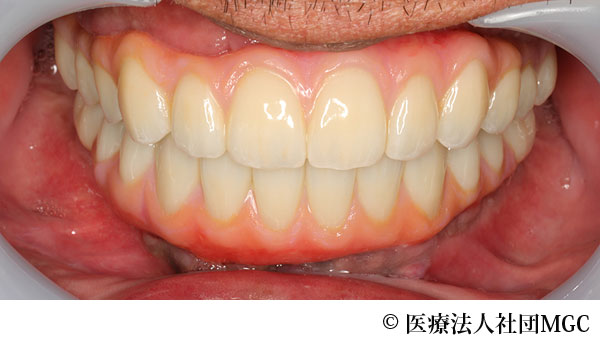

【症例5】上下All-on-4(オールオンフォー)

- 治療前

- 治療後

- 治療名

- 上下All-on-4(オールオンフォー)

- 費用

- 7,208,300円(税込)

- 期間

- 6ヵ月

治療内容

患者様の症状

歯を全体的にきれいに治してほしいとご来院されました。

治療法

ご相談の結果、患者様の生活の質(QOL)を向上させ、しっかり噛め、審美的にも重視した、上下All-on-4(オールオンフォー)を行いました。

治療結果

機能性、審美性ともに改善し、満足していただけました。

※治療結果は患者様によって個人差があります。

治療を行う上での注意点(リスク・副作用)

インプラント周囲炎の可能性、まれに歯が欠ける可能性があります。